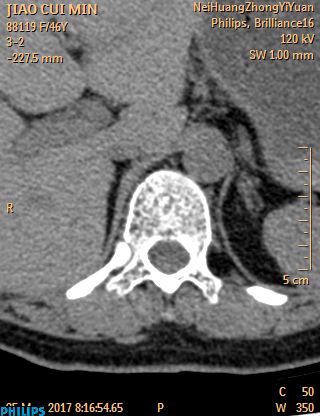

CT52705:肾上腺腺瘤?

病人女,50岁左右,体检发现右侧肾上腺病变,无明显症状。平扫+增强 -------------------- 平扫 --------------------

右肾上腺区可见软组织密度结节。密度较均匀,边缘清楚,中度强化,考虑:右肾上腺腺瘤。

右侧肾上腺腺瘤